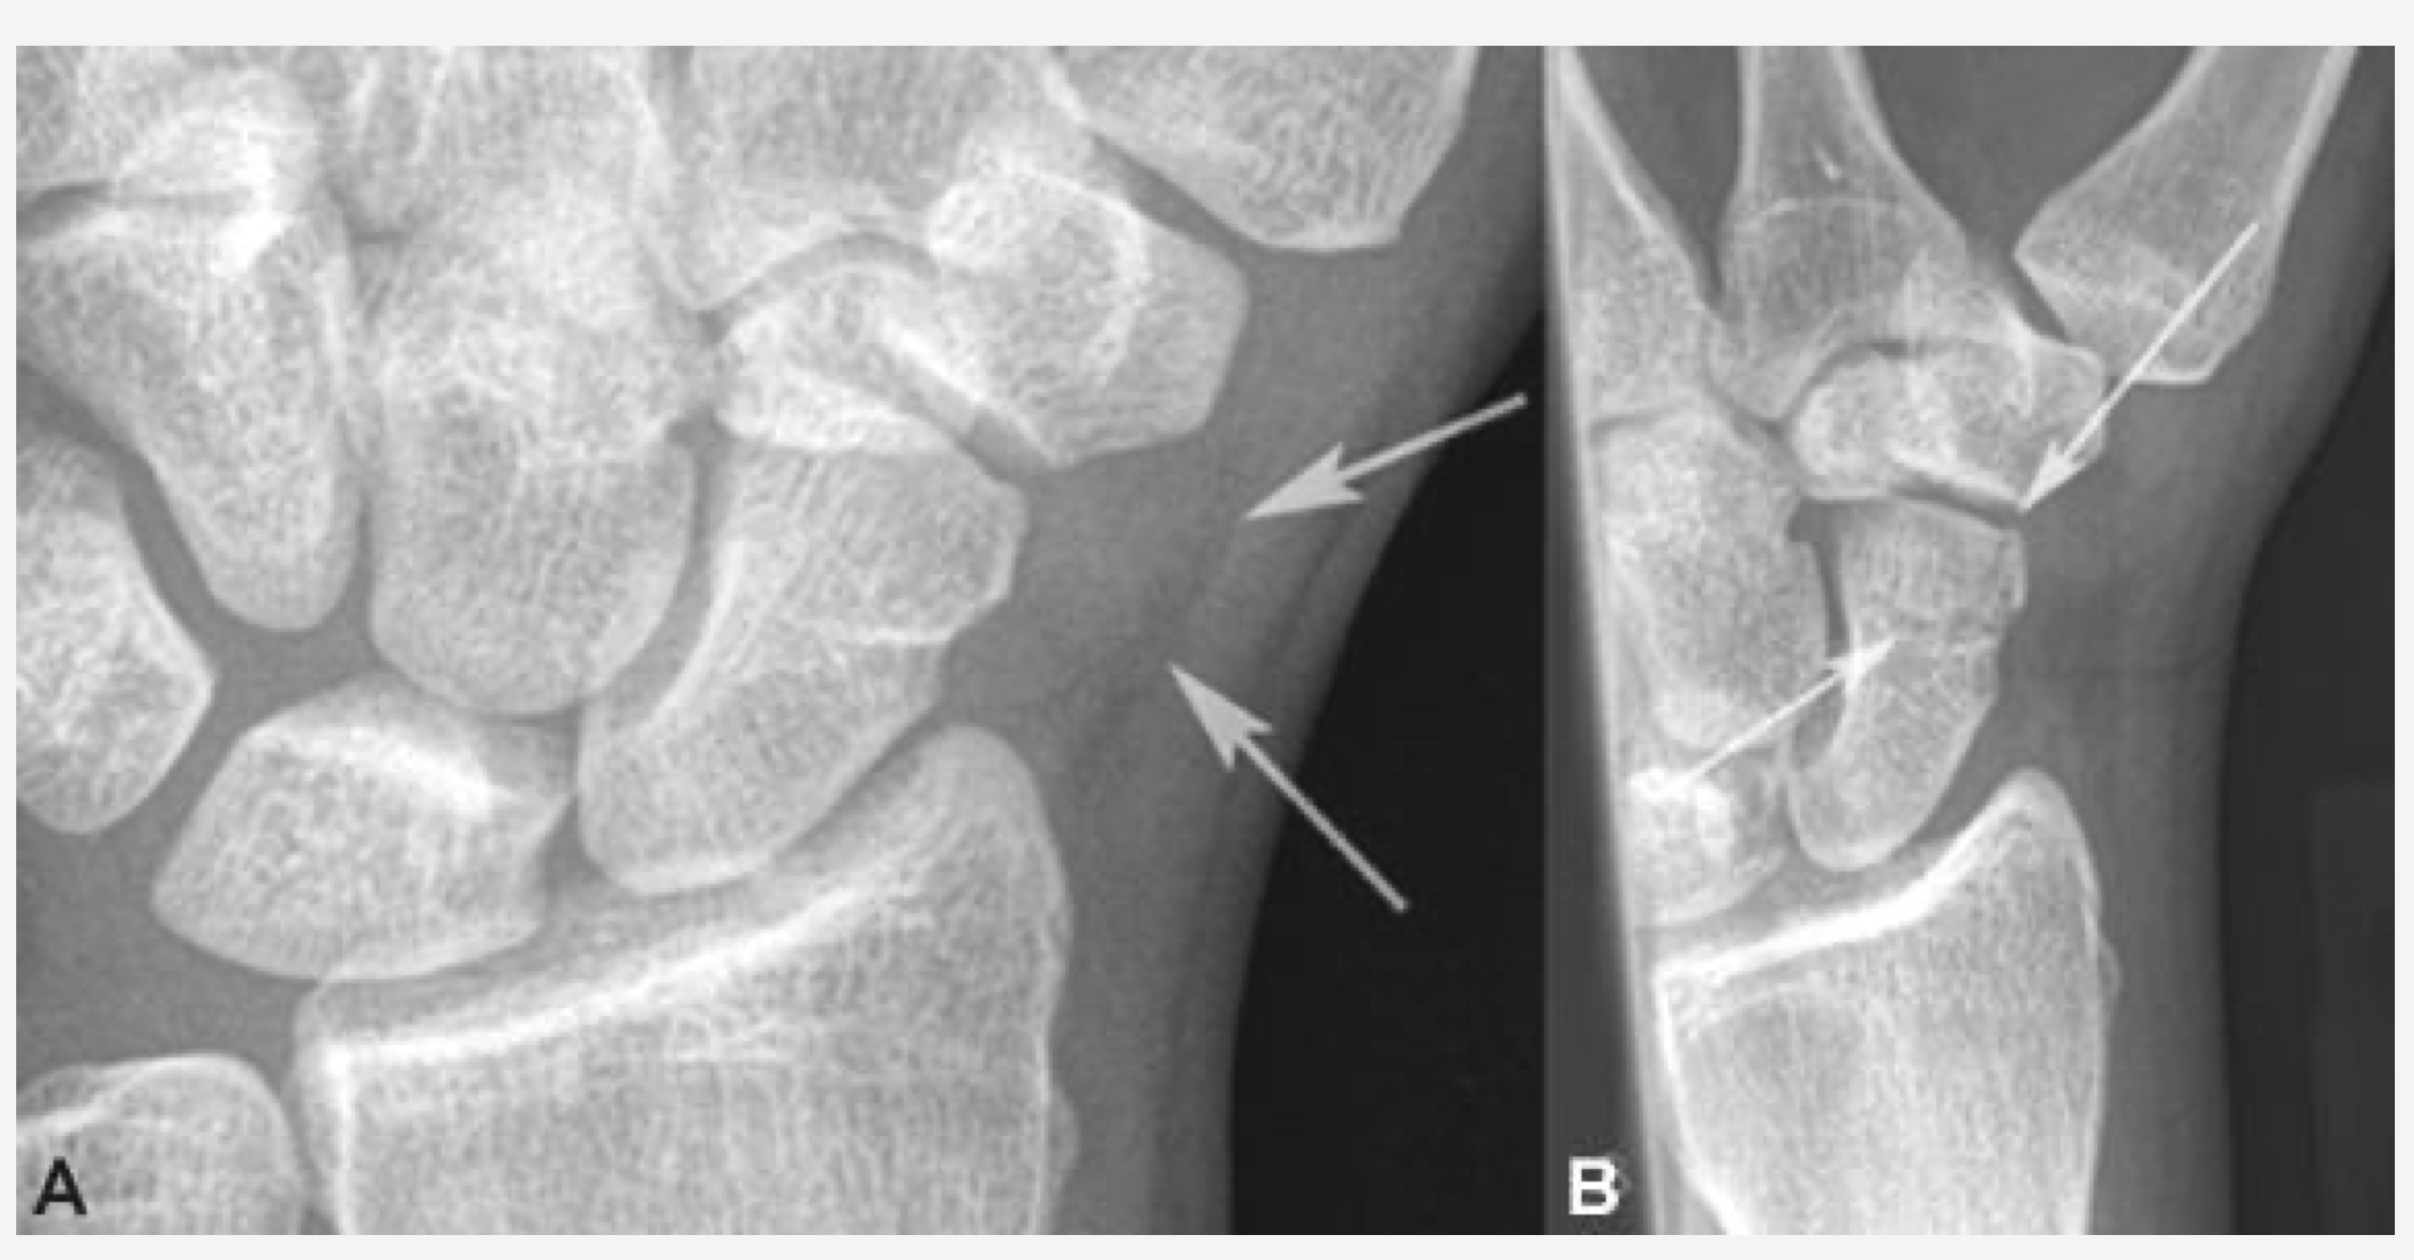

Should demonstrate scaphoid fat stripe

scaphoid fat stripe

looks black, sign of fracture or dislocation. On PA and oblique wrist projections

why does a fractured scaphoid become more apparent after it occurs

it can cut off the blood supply. Also once bony callus starts to form

PA/PA Axial Scaphoid-Ulnar Deviation

Patient is positioned same as PA wrist except hand is flat on IR

Wrist is in ulnar deviation

Forearm remains stationary

Hand is deviated towards the ulna

1st metacarpal is aligned w/ radius

CR centered to scaphoid

2cm distal & medial to radial styloid process

- Base of anatomical “snuff box”

Collimation can be closer than for “regular” PA wrist

CR may be angled toward the elbow

10-15 o or 20° (Stetcher Method)

evaluation criteria for PA/PA Axial Scaphoid-Ulnar Deviation

Scaphoid clearly seen without superimposition

10° to 15° CR angle (elongates scaphoid)

Scaphoid fat stripe demonstrated

1st metacarpal is aligned with the long axis of the forearm

Indicates proper ulnar deviation